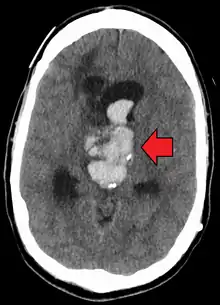

| Axial CT scan of a spontaneous intracranial hemorrhage | |